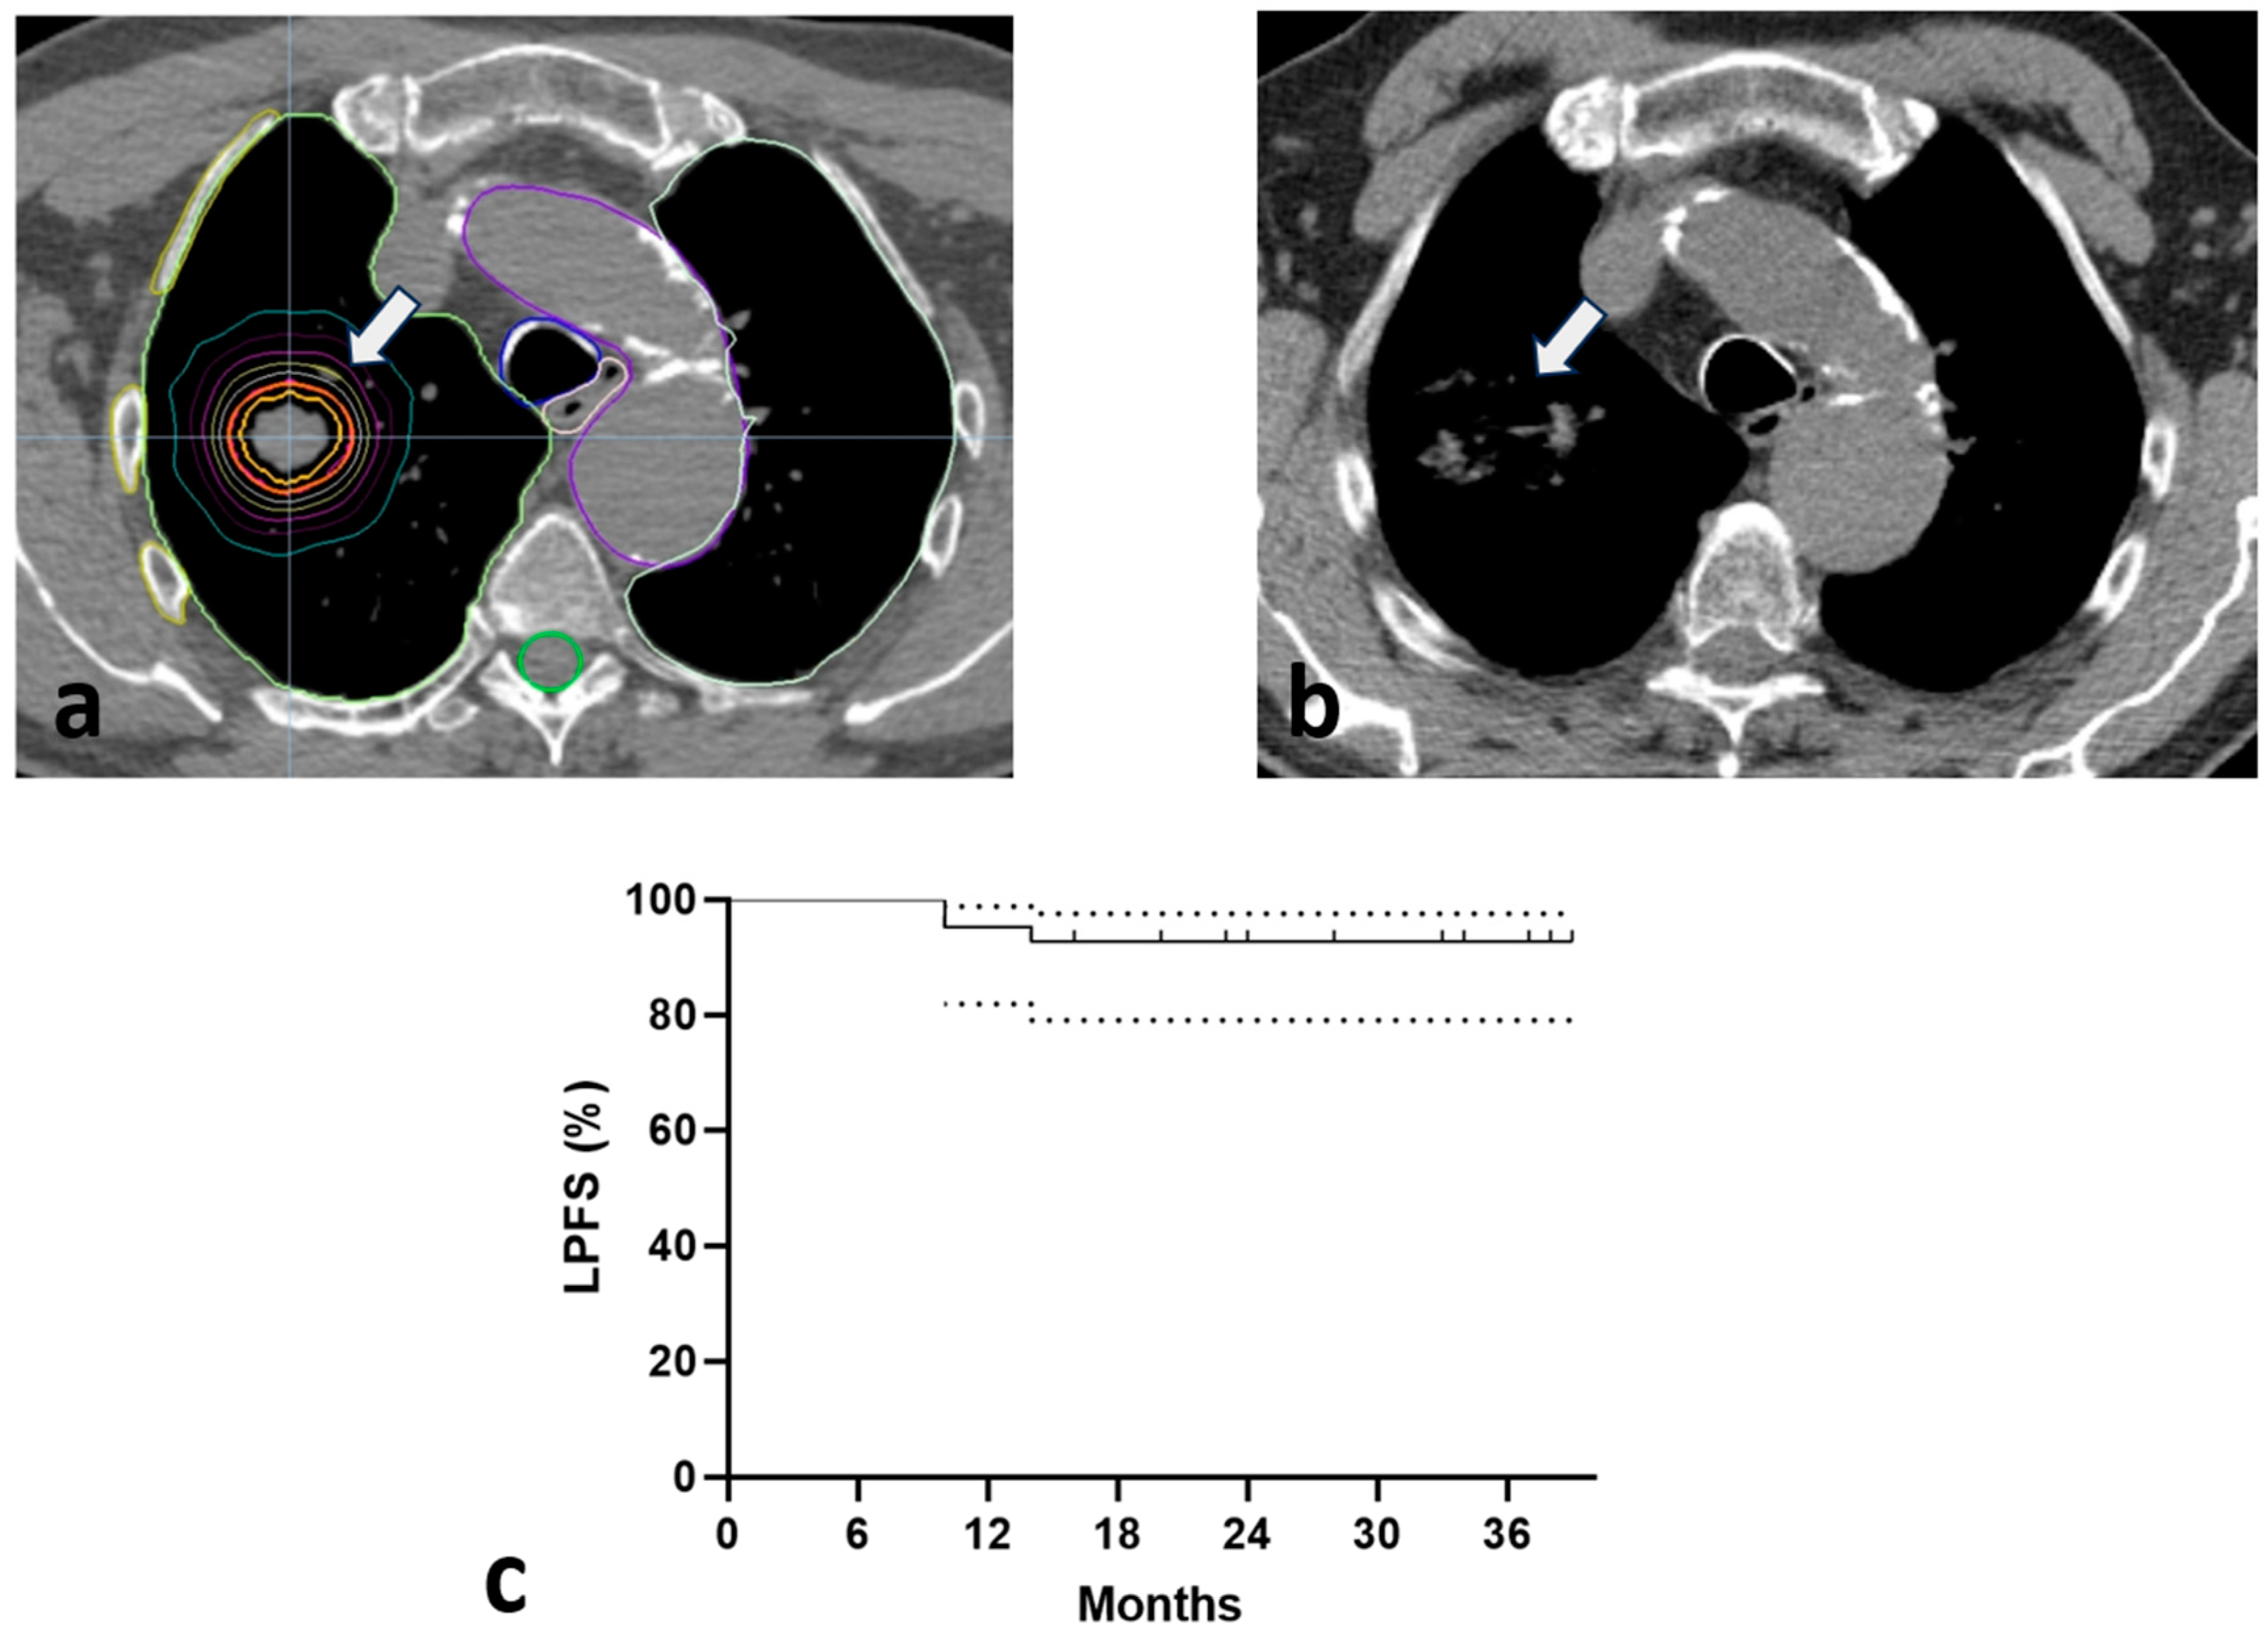

3.3. Survival

| Survival rates (3-year) | ||

| Overall survival | 37 | 90.2% |

| Local progression-free survival | 38 | 92.6% |

| Metastasis-free survival | 38 | 92.6% |

| Progression-free survival | 36 | 87.8% |